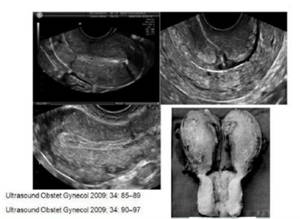

(图:剖宫产子宫瘢痕缺陷)